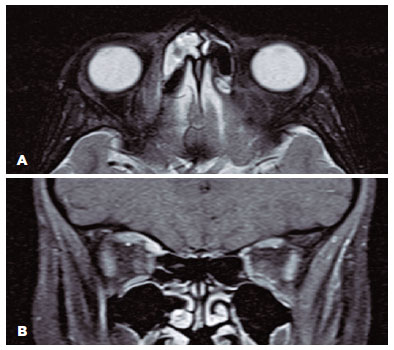

A computed tomography scan with contrast of the orbits and paranasal sinuses demonstrated pan-sinusitis and was suggestive of superomedial subperiosteal abscess in the right orbit (Figure 2). The patient was admitted for medical management and possible combined endoscopic sinus surgery and drainage of the subperiosteal abscess. Upon admission, she received intravenous administration of ceftriaxone and clindamycin in addition to dexamethasone 8 mg at admission and two more doses every 12 hours.

14-fig02.jpg)

In our report, the clinical presentation with the initial CT findings masqueraded the superior oblique myositis as a subperosteal abscess; hence, the case was labeled as such. The close approximity of the superior oblique muscle to the medial orbital wall with the intense inflammation made it difficult to identify distinct borders between the structures and misled the diagnosis to subperiosteal abscess. However, the dramatic response to the initial dexamethasone dose and the relapse after its effect has waned influenced our management plan, and further imaging confirmed the diagnosis of myositis. The use of systemic steroid in orbital cellulitis is controversial as the final outcomes are almost the same. Some authors recommend its use from the start to shorten the hospital stay and hasten the recovery, while others find it unsafe to suppress the patient’s immunity under an infectious etiology(9). In this case, it was advantageous to use a short-term systemic steroid therapy that helped us to diagnose superior oblique myositis.